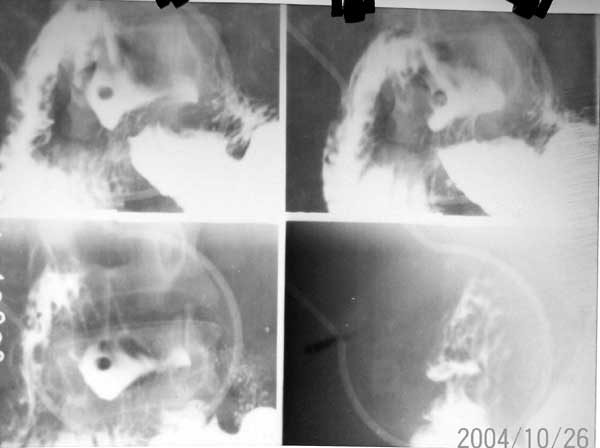

标题: X0127:[讨论]十二指肠球部病变 有结果 [打印本页]

标题: X0127:[讨论]十二指肠球部病变 有结果

考虑息肉,第7幅图像好像可见蒂?不好意思n年没做过胃肠[emb18]

很对不起 抱歉 这是很久以前片子 现无法找到病理结果  当时诊断是 布氏腺增生 仅供参考

球部充盈缺损,有蒂相连。良性点位息肉可能性大。其它就留给胃镜吧

2004/10/26的片子,一般经验,小的称息肉,大得叫腺瘤。

十二指肠布氏腺增生症

这是lihuuuu说的结果

单发布氏腺增生与十二指肠腺瘤发病率都较低 x线鉴别困难

位置形态应该是布氏增生,很罕见.